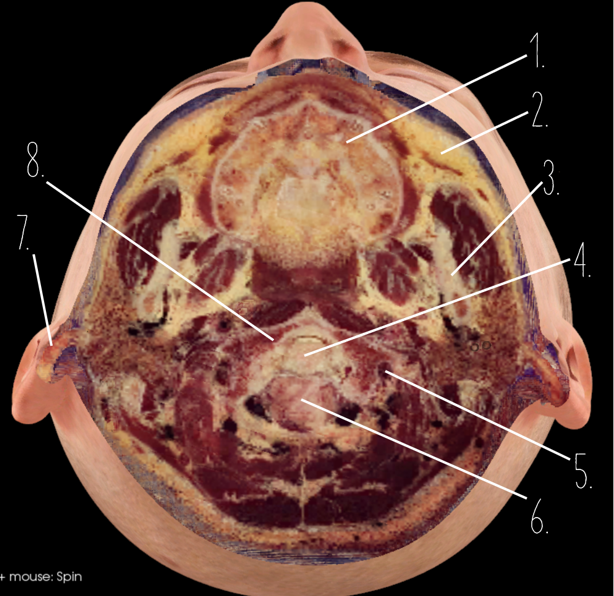

1?

Nasal Bone

2?

Maxillary Sinus

3?

External Acoustic Meatus

4?

Pons

5?

Cerebellum

6?

Mastoid Air Cells

7?

Mandibular Condyles

8?

Sphenoid Bone

9?

Maxillary Bone